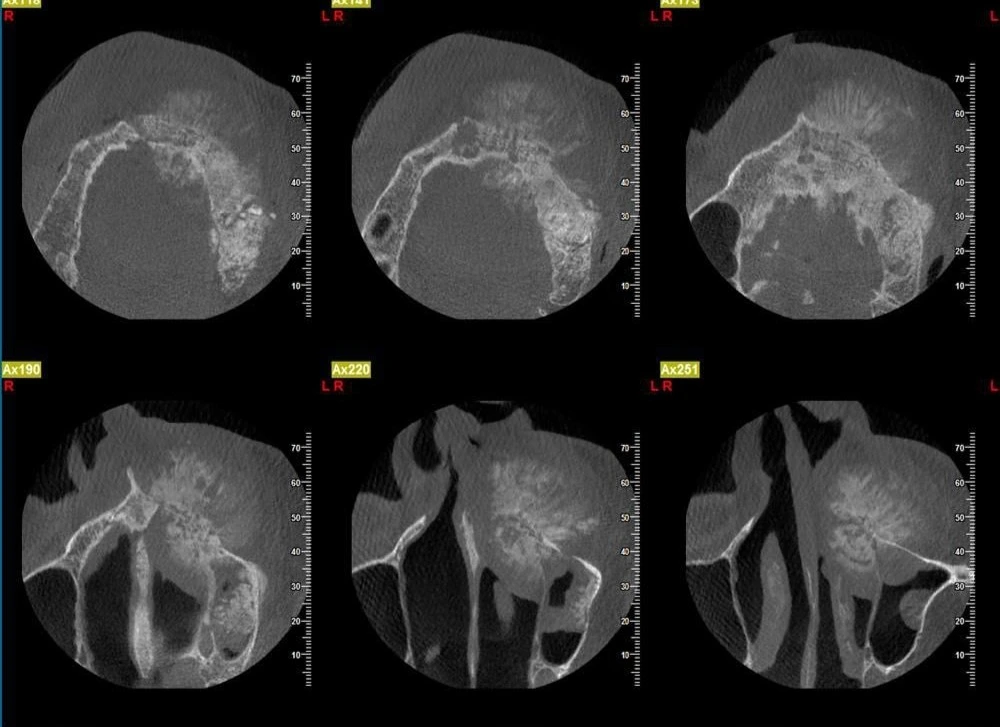

تصویربرداری تخصصی

رادیوگرافی دندانی (پانورامیک): ارزیابی اولیه کیستها و تومورهای فک.

سیتی اسکن سهبعدی (CBCT): تصویربرداری دقیق حجم، مرز و رابطه ضایعه با ساختارهای مهم مانند عصب، سینوس و دندانها.

انجام رادیوگرافی یا CBCT یا MRI در مرکز تصویربرداری.

بررسی تصاویر توسط جراح و تعیین نیاز به بیوپسی.